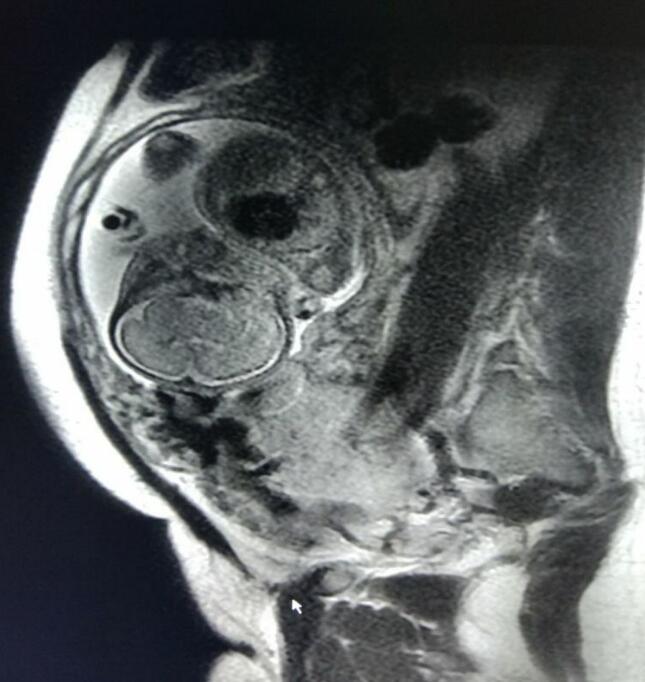

凶险性前置胎盘是指既往有创伤史,本次妊娠又是前置胎盘,胎盘附着子宫前壁前次手术的瘢痕处,由于局部瘢痕的肌肉非常薄弱,在胎盘的生长过程中,发生胎盘植入风险较大,胎盘有可能向子宫深部肌肉植入,甚至穿透植入,常发生难以控制的致命大出血,瞬间出血量可达数千毫升,严重危及母儿生命。

梧州市工人医院产科日前联合介入室、超声科、麻醉科完成了2例腹主动脉球囊阻断下辅助凶险性前置胎盘剖宫产术,取得良好的效果。介入室医师根据术前MRI图像选定合适球囊直径,在超声监视下于剖宫产术前将球囊导管引入腹主动脉内肾动脉开口与腹主动脉分叉之间,固定导管鞘和球囊导管。之后在联合麻醉下行剖宫产术,选择尽量避开前置胎盘的子宫切口切开子宫,娩出胎儿的同时立即充盈球囊阻断腹主动脉,用药物促进宫缩,徒手剥离胎盘并尽量清除植入肌层的胎盘组织,采用可吸收线局部缝扎、折叠缝合、CHO四边形缝合和B-Lynch缝合以控制产后出血。腹主动脉球囊阻断后,术中出血量和输血量明显减少,术野清晰,利于手术操作和精准止血,保住了患者子宫。

在腹主动脉下段预置球囊的全程都是在超声监视下进行,球囊送到位置后进行预扩张,用超声监测到双肾动脉血流通畅,而腹主动脉下段无血流回声,确定球囊放置到位,即固定球囊导管,尽量避免辐射,保证了胎儿安全。该技术在广西区内处于领先水平。